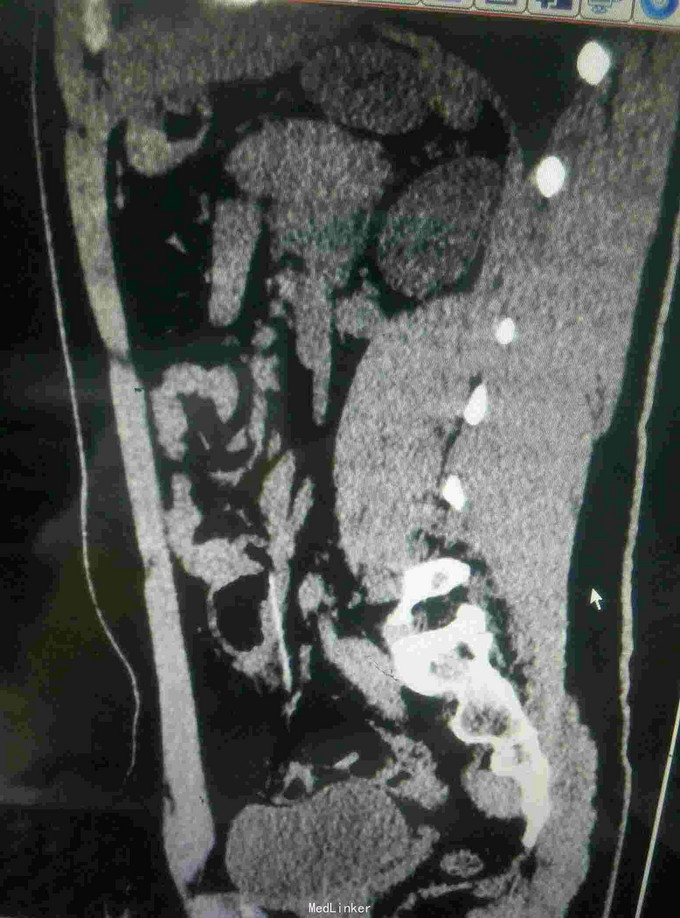

患者,男,16岁,酒后吞食异物后出现疼痛2小时急诊入院

查体:腹部疼痛不适,无明显腹膜刺激征 辅助检查:腹部彩超未见明显异常,胸片可见右肾区异物,CT如图所示

诊断:回肠异物合并贯通伤 治疗:急诊手术异物取出,如图所示。